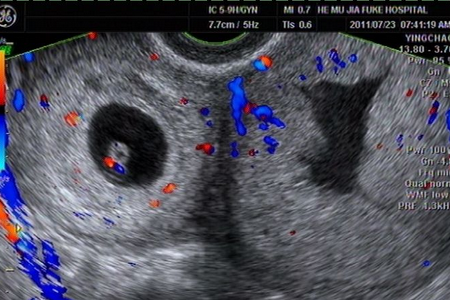

产后一些妈妈感觉到腹部有下坠和疼痛等症,去医院检查后发现是有盆腔积液。那么,产后盆腔积液是怎么引起的呢?

产妇分娩后,体内激素下降或者在产后42天时处于排卵期等,就会导致少量的盆腔积液出现,这种为正常的生理现象,妈妈们不用担心,它会随着产妇内分泌的恢复或者月经结束,积液会自行吸收。

女性在生产后,身体虚弱,免疫能力低下,宫颈口处于扩张状态,此时,若不注意生殖部位的清洁卫生或过早进行性生活等,均可引发细菌滋生而导致盆腔感染发炎,出现盆腔积液。

如果产后子宫内有残留物,如胎盘、胎膜残留等,也会造成持续阴道出血以及感染产后盆腔炎,出现盆腔积液的情况。

如果妈妈在产后急于瘦身,不当使用束腹带,会导致盆腔血流不畅,再加上饮食过少,营养不足,抵抗力下降,所以容易诱发盆腔炎,进而出现盆腔积液。